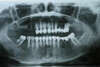

Cas n°5

Patient ne supportant plus le fait d'avoir deux complets à déposer chaque jour. Les complets sont plus communéments appelés des appareils dentaires.

Solution : remplacement de deux prothèses complètes (appareils dentaires) par deux prothèses transvissées sur 6 implants en haut.